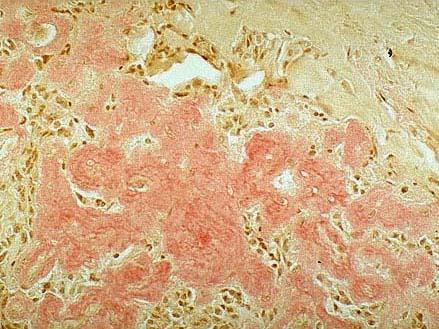

问题 图1为甲状腺髓样癌的镜下观,图2为该肿瘤刚果红染色镜下观,由此二图可知该肿瘤的哪些特征 ( )

选项 A.肿瘤间质中可见淀粉样物质沉积 B.肿瘤组织由实性细胞巢或片块构成 C.肿瘤外围可见残留的甲状腺滤泡 D.肿瘤细胞异型明显,核分裂多见 E.常见出血,坏死囊性变

答案 ABC